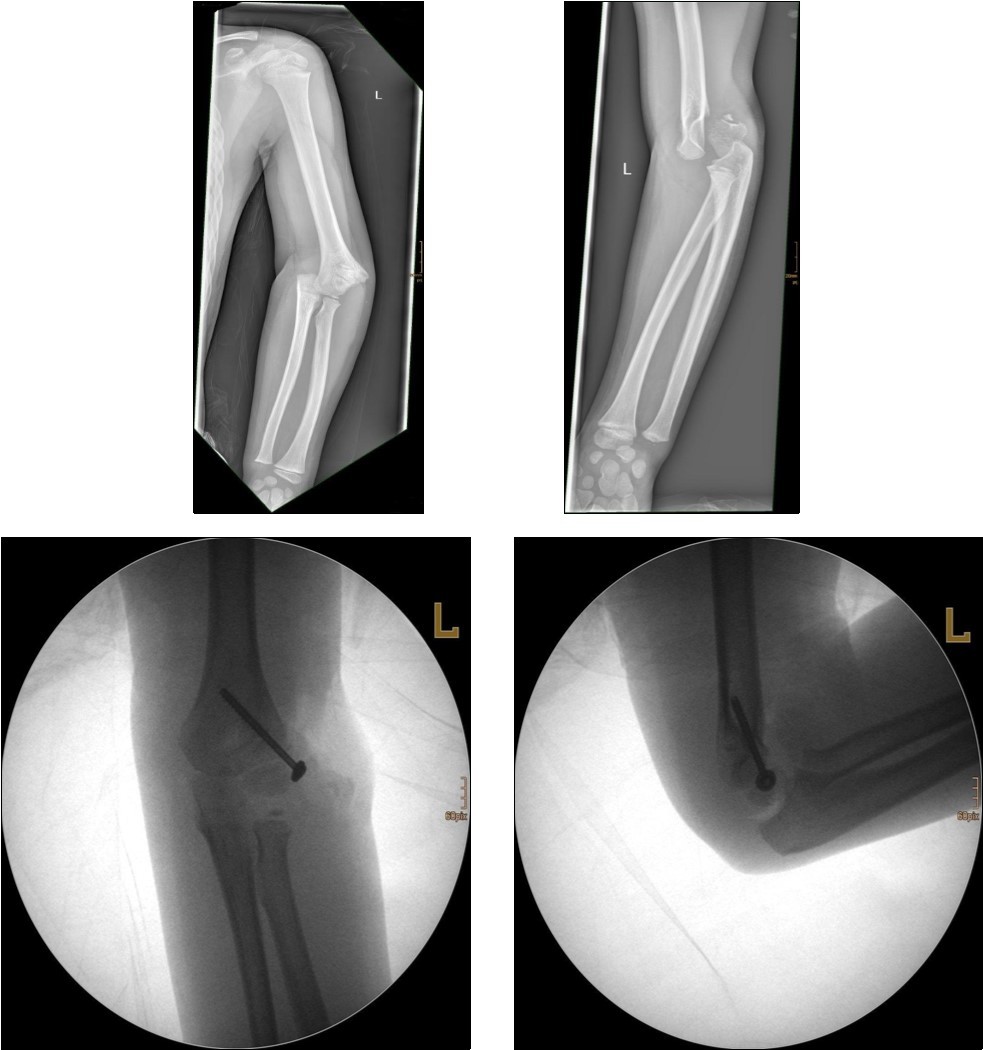

Non-displaced and stable fractures may be treated by cast immobilization with close follow-up, but fractures displaced >2 to 3 mm may indicate surgical fixation 7, 8. Surgical treatment can be done either by closed reduction and percutaneous osteosynthesis or open reduction and osteosynthesis. Figure 3.

Figure 3.9 year old male patient with a elbow dislocation and a dislocated left lateral condyle fracture which was treated by open reduction and osteosynthesis with a screw (personal collection)

Surgical fixation is either by screw, smooth K-wires or both. The K-wires can be buried under the skin or not.

Regarding pin orientation, most authors favor a divergent construct for greater stability.

For 2-pin constructs, maximizing pin divergence at the fracture site provided greater stability in torsional loading and valgus loading. The addition of a third pin in a divergent orientation increases stability compared with 2-pin constructs in valgus, internal, and external rotation loading. The pins must be placed in a bicortical manner, with maximum divergence and spread at the fracture site 10.